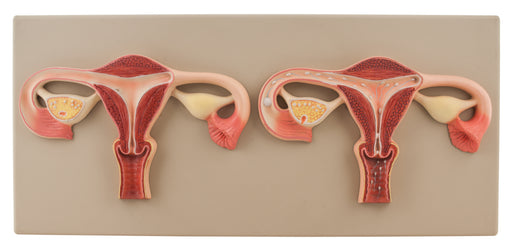

Fertilization Set of 2

This model showing fertilization by two frontal section through the female genital organs. Mounted on base. Supplied with English Key Card. Size 56...